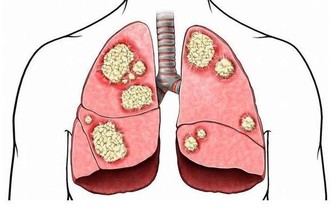

3.結腸癌研究發現久坐和結腸癌、乳房和子宮內膜癌有關。原因還不清楚,

但是有一個說法是過多的胰島素會增進細胞生長。

另一個說法是規律的活動會增進天然抗氧化劑來對抗自由基。